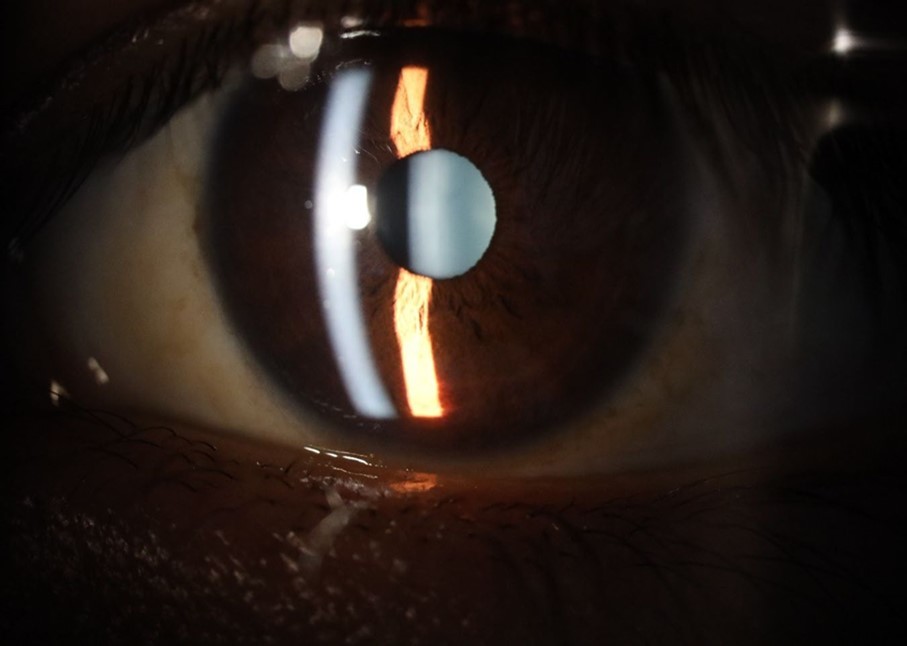

Figure 5.The slit-lamp photograph shows the anterior segment, relatively unscathed, in terms of transparent media (Cornea, crystalline and vitreous).

The slit-lamp photograph shows the anterior segment, relatively unscathed, in terms of transparent media (Cornea, crystalline and vitreous).